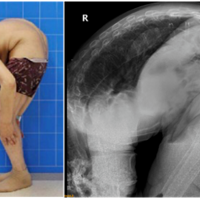

求医28年的“折叠人”出院,最让我感动的却是他的母亲

38300659 2020-07-20 08:53

18789 浏览 查看原帖